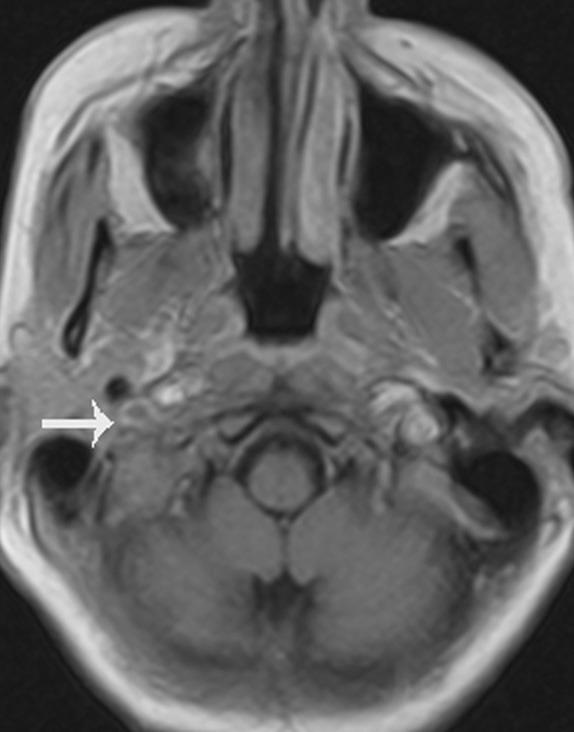

Cerebral venous thrombosis (CVT) is a well-recognized entity, but its clinical presentation is varied and often mimics many neurological disorders, making it a diagnostic challenge. Cerebral venous thrombosis has a wide spectrum of signs and symptoms, which may evolve suddenly or over weeks. It mimics many neurological conditions such as meningitis, encephalopathy, idiopathic intracranial hypertension, and stroke. Cerebral venous thrombosis presenting as multiple lower cranial nerve palsies, are rarely reported. We describe a pregnant lady who presented with sensorineural deafness of the right ear and paralysis of the 9(th), 10(th), and 12(th) cranial nerves on the right side. She was diagnosed to have thrombosis of the right transverse sinus and sigmoid sinus with extension to the jugular vein and confluence of sinuses. She improved with anticoagulant treatment.

脑静脉血栓形成(CVT)是一种广为人知的疾病,但其临床表现多样,常与许多神经系统疾病相似,这使其成为一项诊断挑战。脑静脉血栓形成有广泛的体征和症状,可能突然出现或在数周内逐渐发展。它可模仿许多神经系统疾病,如脑膜炎、脑病、特发性颅内高压和中风。以多发性低位颅神经麻痹为表现的脑静脉血栓形成很少见报道。我们描述了一位怀孕女性,她出现右耳感音神经性耳聋以及右侧第9、10和12对颅神经麻痹。她被诊断为右侧横窦和乙状窦血栓形成,并延伸至颈静脉和窦汇。经抗凝治疗后病情好转。